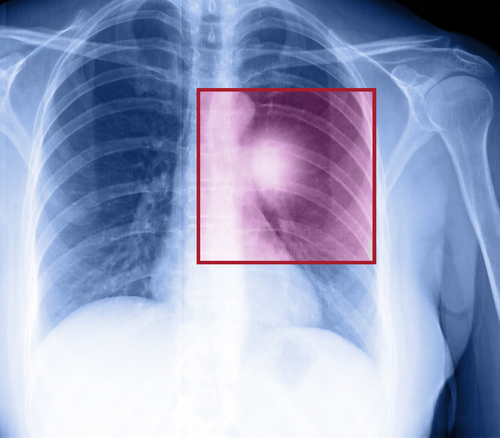

Lung cancer is the most common cancer worldwide.

According to Dr Ravi Gaur, COO, Oncquest Lab, “In last one year we have seen an increase in the number of cases of lung cancer. From May 2016 to April 2017, we have received 273 cases of lung cancer from Delhi-NCR out of which 154 cases were found positive.”Tobacco smoke is the number one risk factor for lung cancer, but non-smokers can get it, too. Of the 4,000 chemicals that are present in cigarettes, over 50 of them are highly carcinogenic, i.e. something that causes cancer.Though exposure to secondhand smoke is again a serious health hazard. It’s not just those who are actively smoking tobacco are affected but passive smokers are also at the receiving end.